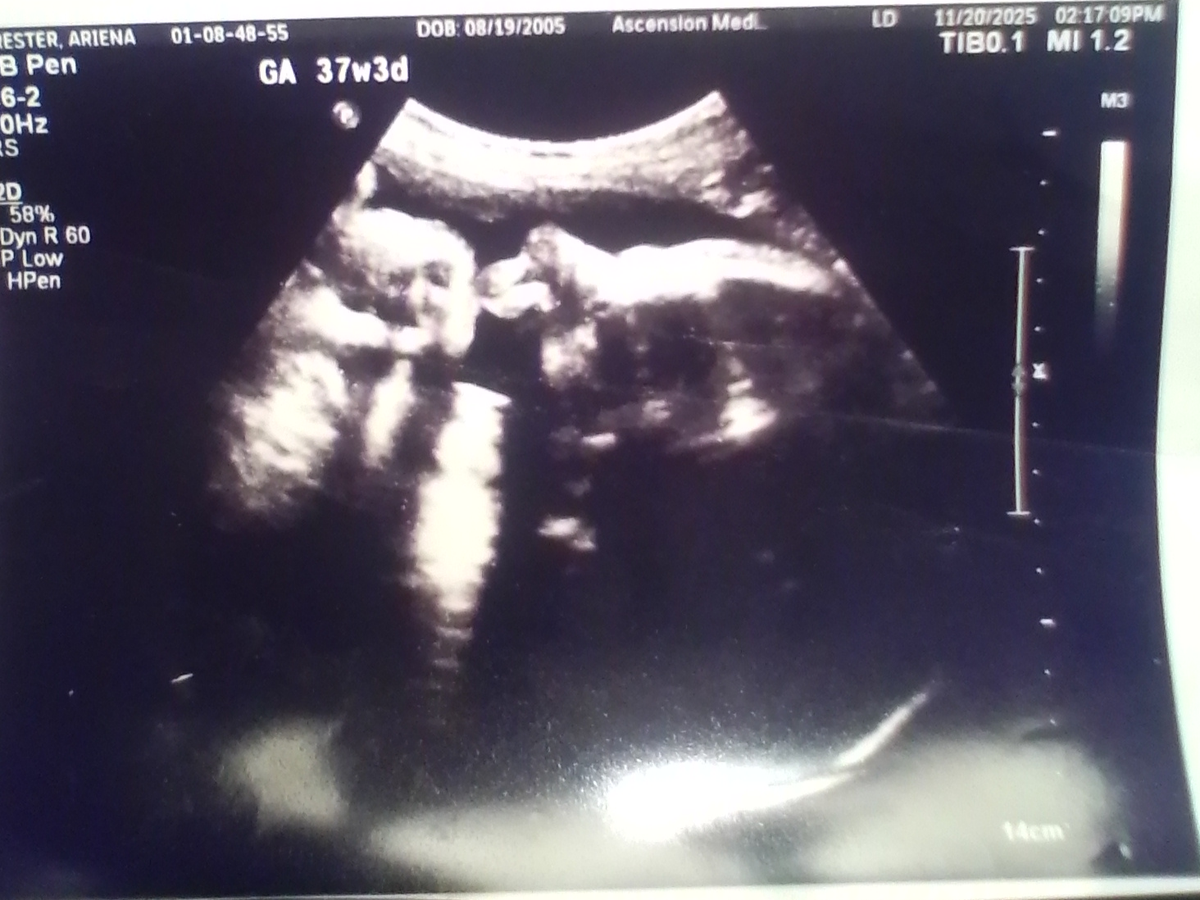

I am currently getting evicted by my landlord, and am due any day now with my baby. I have exhausted my options and unfortunately have not had any luck. I am hoping to get this camper to be able to have a place to live, instead of the huge possibility of being homeless. If anyone could help, I would really appreciate it. The goal is based off what the website says a down payment would be, plus some payments. Thank you to anyone who shares or donates.